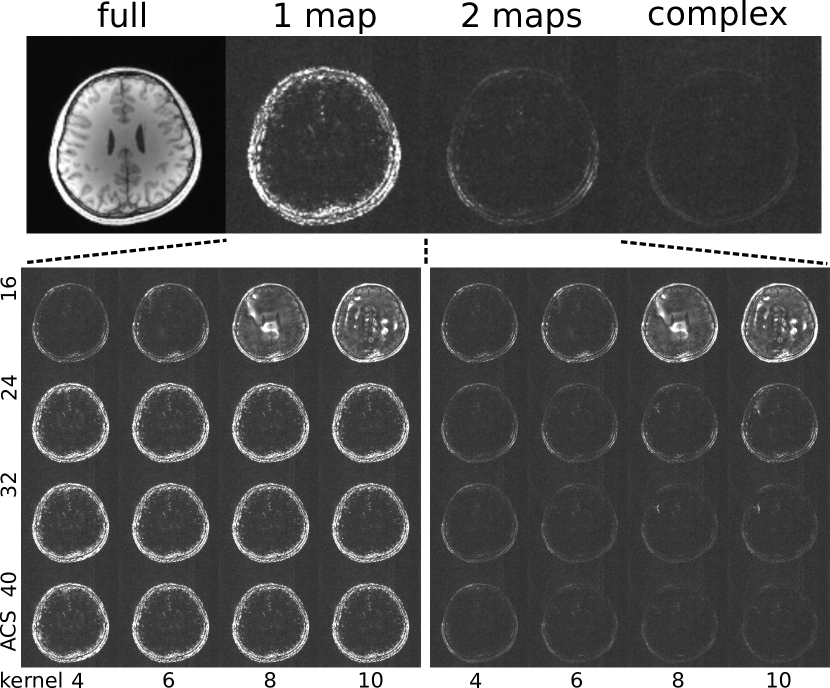

Figure 3: This figure shows the combined residual (unexplained) signal from all channels after projection of the coil images onto different spaces. Top: full signal for comparison (full), real-projection onto the first set of VCC-ESPIRiT maps (1 map), real-projection onto both sets of VCC-ESPIRiT maps (2 maps), complex-projection onto a single set of conventional ESPIRiT maps (complex). Bottom: The impact of the size of the calibration region and the size of the kernel on the quality of the maps is evaluated using a real-projection onto one (left) or both (right) sets using a calibration region (ACS) of size 16x16, 24x24, 32x32, and 40x40 and kernel size of 4x4, 6x6, 8x8, and 10x10. For each case, the residual signals for all channels have been combined into a single image using the root-sum-of-squares method. Relative to the full signal all other images have been scaled up by a factor of five to aid visualization.

Figure 3 shows the results of the projection test for the VCC-ESPIRiT maps. The real projection PRsubscript𝑃𝑅P_{R} of the coil images onto the space spanned by the coil sensitivities shows that the image and coil phase are accurately captured in most parts of the image, but that residual signal occurs in areas with high-frequency phase from fat and blood vessels which cannot be modelled with a single set of smooth maps even with a larger calibration region. With a second set of maps a larger space is spanned and the residual signal can be modelled. Although the quality of the maps degrades if the calibration region is smaller than 24x24 and especially when a large kernel size is used together with a small calibration region, the quality of the single set of VCC-ESPIRiT maps is otherwise relatively robust to the choice of parameters. When using just a single set of maps, increasing the calibration region and the kernel size does not improve the error much. This is because high frequency phase can not be represented well without going to extreme sizes. In contrast, increasing the calibration region and kernel sizes does reduce the error when two sets of maps are used. In our example, for 40x40 calibration region using two sets of maps, while enforcing real-valued result, has comparable error to the case where phase is not constrained. This means that for this case, VCC-ESPIRiT captures well the signal subspace with all its phase variations.